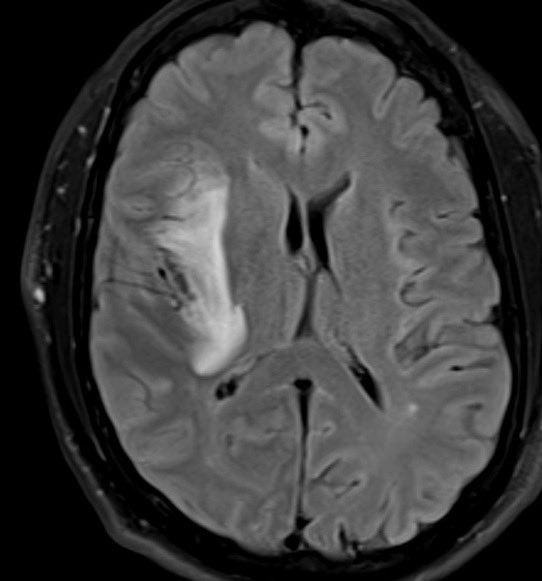

ROC of the week: Herpes encephalitis Findings: confluent FLAIR hyper intense signal involving the right temporal lobe, insula and subgenual cingulate with associated susceptibility artifact

#FOAMrad#FOAMmed#radres#neurorad#radiologypic.twitter.com/4BMDiCf5pF